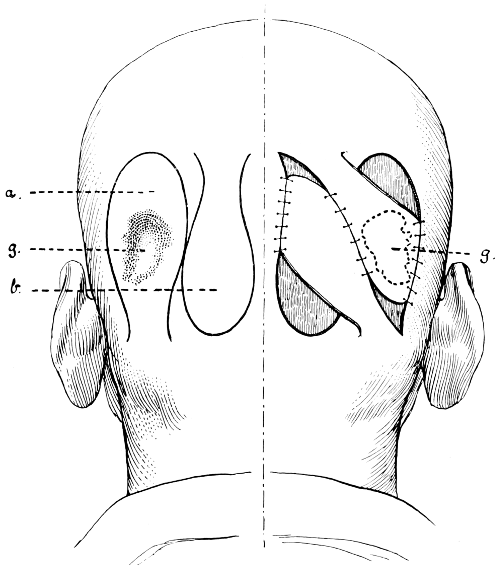

Fig. 1. Cranio-cerebral Topography. 1, The nasion; 2, The inion; 3, The mid-point between nasion and inion; 4, The Rolandic fissure; 5, The superior temporal crest; 6, The inferior temporal crest; 7, The Sylvian point; 8, The anterior horizontal limb of the Sylvian fissure; 9, The vertical limb of the Sylvian fissure; 10, The posterior horizontal limb of the Sylvian fissure; 11, The parietal prominence; 12, The malar tubercle; 13, The lambda; 14, The first temporo-sphenoidal sulcus; 15, The external parieto-occipital sulcus; 16, The lateral sinus; 17, 17, 17, The level of the base of the cerebrum; 18, The external auditory meatus; 19, 19, Reid’s base-line. (Reproduced, by the permission of Mr. H. K. Lewis, from the author’s work on ‘Landmarks and Surface-markings’.)

Fig. 2. Cranio-cerebral Topography. 1, 1, Reid’s base-line; 2, 2, A line parallel to the above at the level of the supra-orbital margin; 3, The middle meningeal artery; 4, The anterior branch; 5, 5, 5, The three sites for trephining; 6, The posterior branch; 7, The site for trephining; 8, The point for trephining to reach the descending horn of the lateral ventricle; 9, The lateral sinus; 10, The inion; 11, The mastoid process; 12, Macewen’s suprameatal triangle; 12a, The mastoid antrum; 12b, The facial nerve; 13, The suprameatal and supramastoid crests; 14, 14, The temporal crest; 15, The temporal fossa; 16, The external angular frontal process; 17, The tendo-oculi attachment; 18, The lachrymal groove. (Reproduced, by the permission of Mr. H. K. Lewis, from the author’s work on ‘Landmarks and Surface-markings’.)